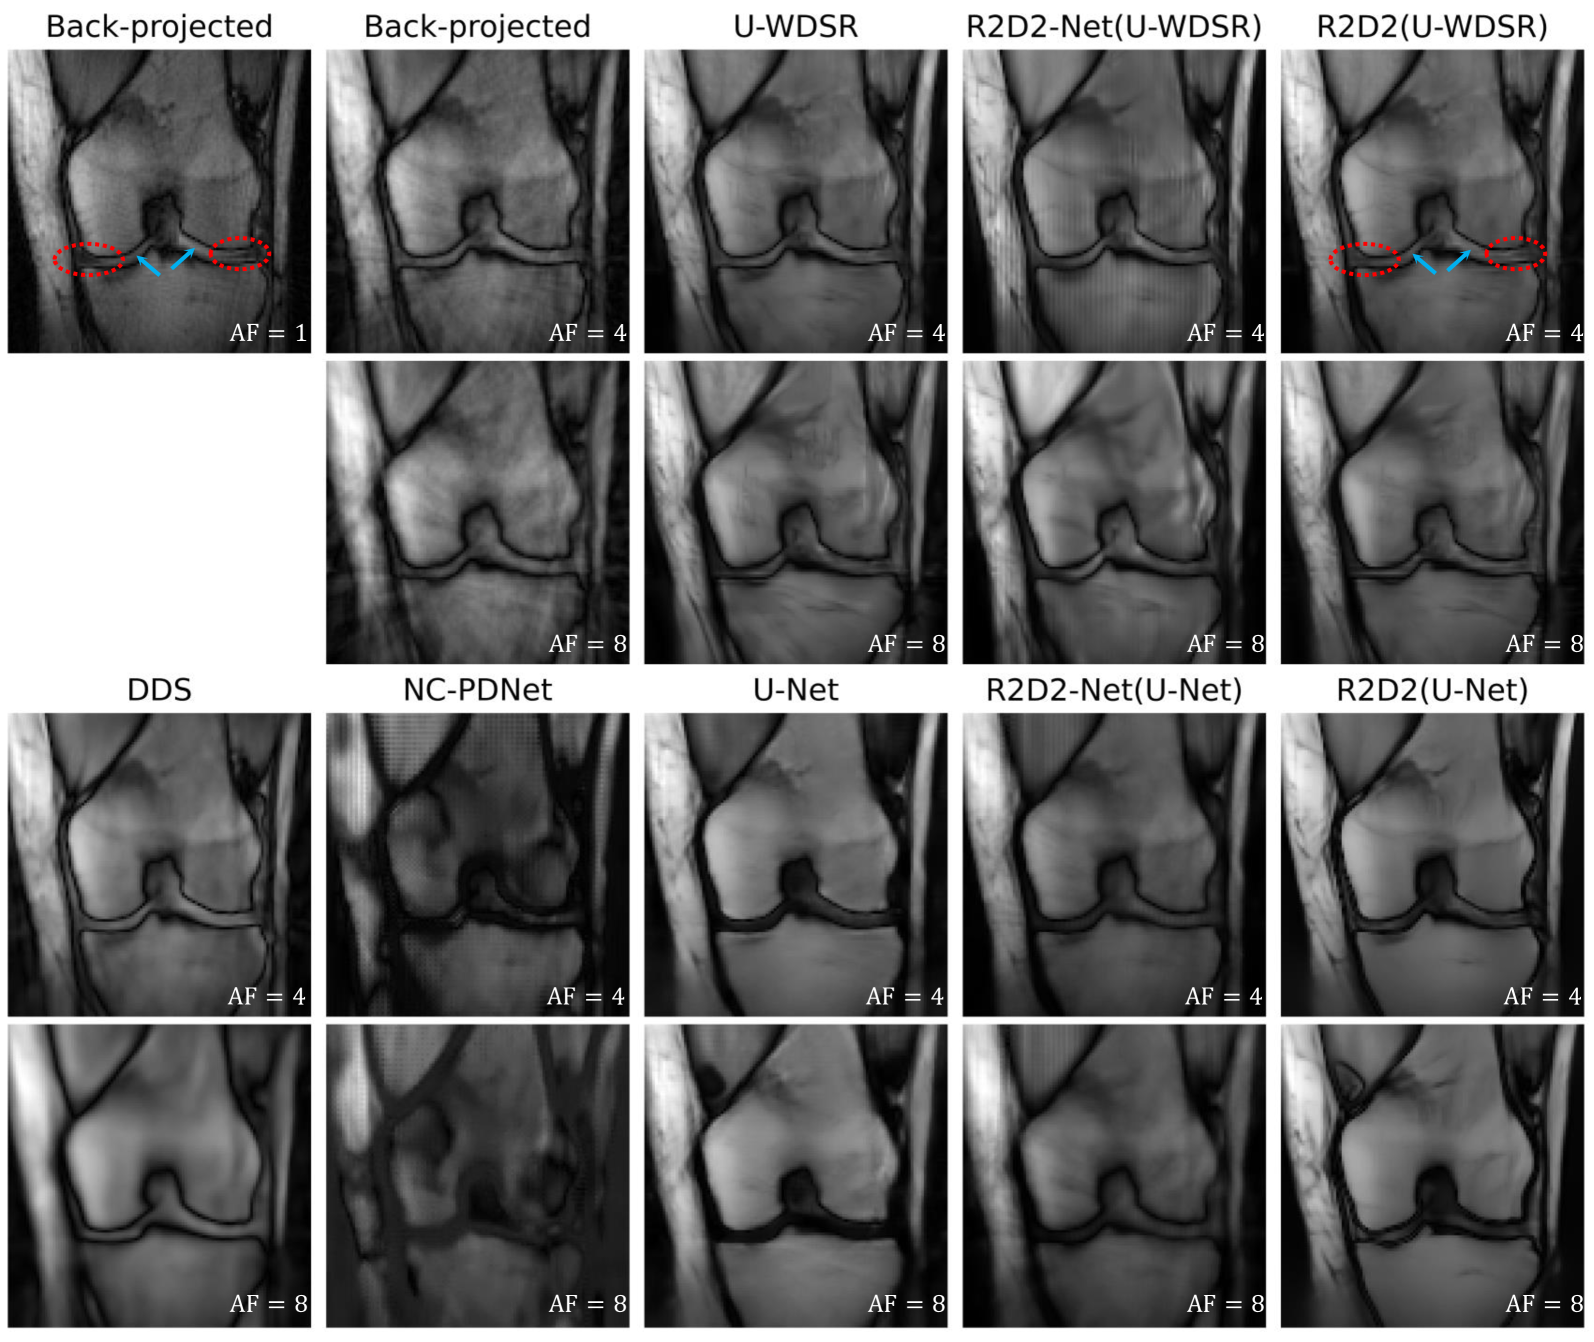

Figures 5 and 6 present the visual results of various comparison methods for and , respectively. This enables evaluating the changes in reconstruction quality with increasing AFs. results also provide a per-method reference for the results and the reader is invited to flip between Figures 5 and 6 for a comparison at a glance. In each figure, the first and fourth rows display the reconstructed images (with values of PSNR (dB) reported in the bottom left of each panel), while the second and fifth rows show the corresponding Regions Of Interests (ROIs). Dotted ellipses highlight areas with subtle differences between the reconstructed, GT, and back-projected images. The third and sixth rows provide error maps relative to the GT image. The images displayed and reported PSNR values are at iteration for R2D2(U-Net) and for R2D2(U-WDSR).

We firstly focus on . The back-projected image shows significant blurring, noticeable artifacts, and substantial errors. Methods like U-Net, DDS, NC-PDNet, and R2D2-Net(U-Net) exhibit improvements in structural detail over the back-projected image but still suffer from notable reconstruction errors. The U-WDSR architecture provides a noticeable jump in visual quality over U-Net, similar to R2D2(U-Net) and R2D2-Net(U-WDSR). R2D2(U-WDSR) provides the best performance, effectively preserving fine structural details and minimizing reconstruction errors. These results are in line with the quantitative analysis (see Section V-E).

All algorithms exhibit significant improvements at , but the general conclusions drawn at remain. We note that DDS produces a noisy output, with a PSNR not superior to that of the back-projected image. Interestingly, R2D2(U-WDSR) exhibits the highest stability across accelerations, further confirming the results of the quantitative analysis.

Figure 9 illustrates the back-projected images with and reconstructions with all R2D2 and benchmark methods at and . For the reconstruction of R2D2 methods, we use the estimated images at iteration of R2D2(U-Net) and iteration of R2D2(U-WDSR) as no improvement results from using further iterations. Notably, while provided for reference, the back-projected image at is not a true GT image, since it is not properly reconstructed but only back-projected, affected by an imperfect calibration setup. In fact, it exhibits noticeable artefacts originating in the radial k-space sampling pattern. We also note that the DR for this sample is only , which limits the achievable visual quality across reconstruction methods. In particular, at , improvements of R2D2 across iterations are a priori expected to be subtle (see Section V-H).

Overall, NC-PDNet fails to reconstruct the knee image properly, both at and . This is mainly due to the domain shift problem [42], where the U-Net-based calibration module (unique to NC-PDNet across all methods compared) struggles to generate accurate sensitivity maps for the real data. DDS shows noticeable blurring and loss of texture detail, with a particular degradation at . R2D2-Net(U-WDSR) introduces strong “vertical-stripe” artefacts, and brightness issues at . R2D2-Net(U-Net) mitigates these issues, but at the expense of an increased blurriness. U-Net provides blurred reconstructions and significant loss of structures, issues that R2D2(U-Net) strongly mitigates. While the U-WDSR architecture provides much sharper reconstructions than U-Net, without noticeable loss of structure, some “vertical-line” artefacts do appear, particularly at . R2D2(U-WDSR) delivers the best reconstruction overall, in terms of sharpness, recovery of faint structure, absence of obvious artefacts, and stability across accelerations. It provides the reconstruction of the cartilage (blue arrows) and menisci area (red ellipses) that is most faithful to the back-projected image at .